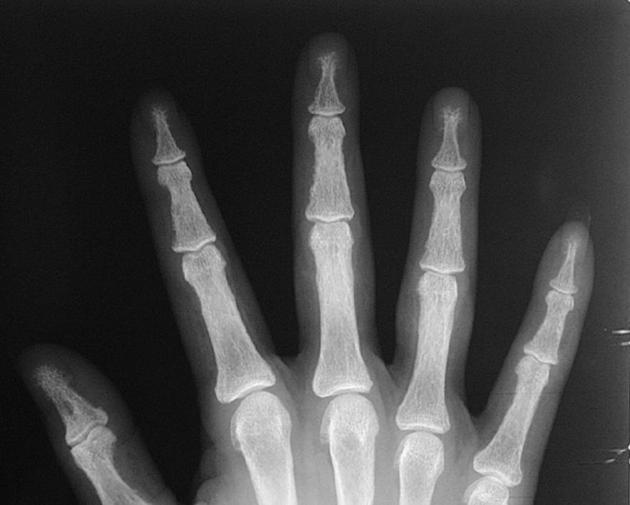

pencil in cup deformity

Psoriatic Arthritis

Almost always accompanies skin disease, especially nail changes

Mostly involves DIP joints of hands > feet